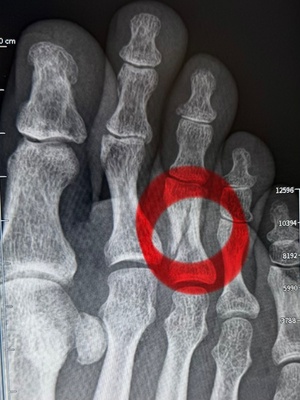

9月15日に折れた私の右足中指(判明したのは9月29日)。日常生活でほとんど誰にも気づかれることもなく、歩いています。

そんな簡単には治らないものなんですね。これでも、前回のレントゲン写真と比べて拡大して見ると、うっすらとくっつき始めているんです。

「きれいにくっつくにはまだまだ時間はかかりますよ」と医師に言われました。歩いているし、想像以上に自宅などでもぶつけたり、負担がかかる動きをしているものなんです。もうしばらく付き合うしかなさそうです。